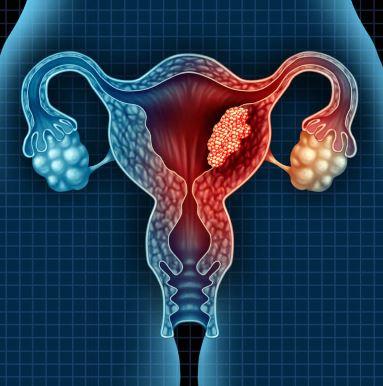

"Why Choose Our Clinic for Your Obstetrics & G...

"Discover the Top 10 Gynecologists in Pimpri-Chinc...

"Find the Best Gynecologist in Pimpri Chinchwad fo...

"Get Personalized Gynecological Care in Pune" Our ...

"Experience Exceptional Gynaecological Care in Pun...

"Find the Best Obstetrics & Gynecology Service...

"Find Your Perfect Gynecologist in Pimpri Chinchwa...

May 15 "Get the Best Gynecological Care in Pune Ne...